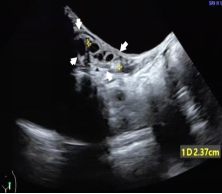

发育的卵巢,可见多个直径≥4 mm 的卵泡

(白色箭头所指)